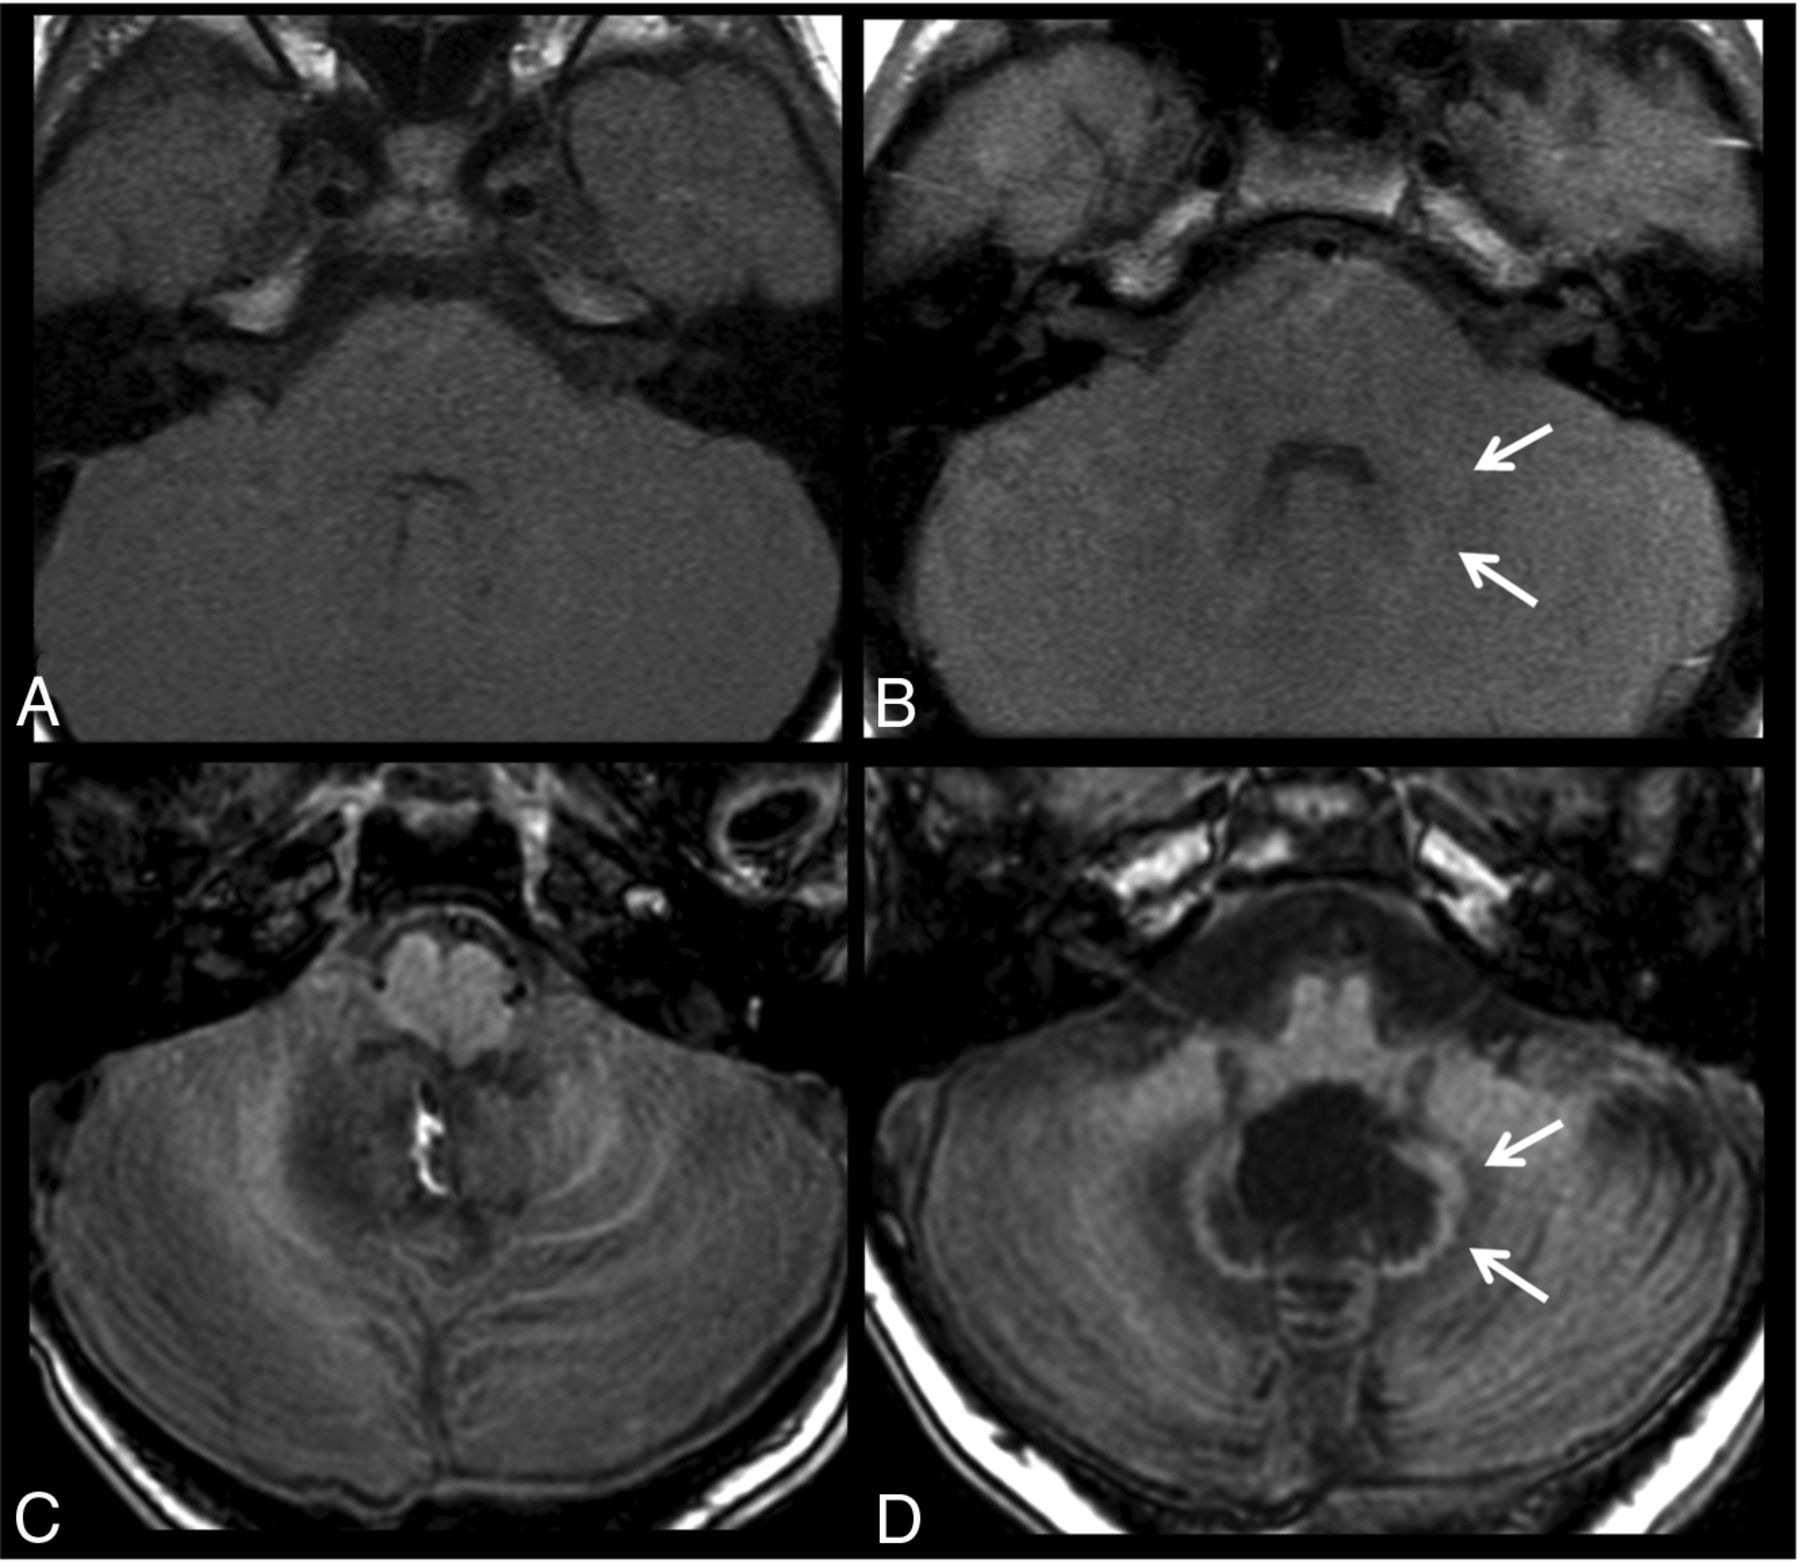

Figure 2 shows a comparison of 2 patients after 20 injections, one with no treatment variables and 1 patient with medulloblastoma after radiochemotherapy. Figure 3 shows images before and after 10 gadobenate dimeglumine injections in a patient with no treatment variables and a second patient with a medulloblastoma, after surgery and radiochemotherapy.

T1-weighted images acquired before (A and C) and after 10 gadobenate injections (B and D) in a patient being followed for a mass at the craniocervical junction with only surgical therapy (A and B) and a patient with medulloblastoma after an operation and radiochemotherapy (C and D). No signal change can be seen in the dentate for the patient without RCTX, while the patient with RCTX already shows signal changes after 10 injections.